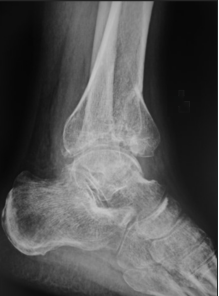

目前应用最广的是踝关节骨关节炎分期为Takakura-Tanaka分期:

0期:踝关节平行,无关节炎征象;

Ⅰ期:踝关节平行,无关节间隙狭窄,有早期软骨下骨硬化或骨赘形成;

Ⅱ期踝内侧关节间隙狭窄,无软骨下骨接触;

Ⅲ期又可分Ⅲa期和Ⅲb期:

Ⅲa期 踝内侧间隙消失,软骨下骨接触面局限于内侧;

Ⅲb期 踝软骨下骨接触延伸至距骨穹窿部;

Ⅳ期 踝关节间隙消失伴全部软骨下骨接触。

影像学检查:最重要的诊断依据:如X片检查、CT检查、MRI检查、超声波检查等,其中X片及CT对诊断尤为重要。

X片:检查可以显示关节间隙狭窄、骨赘形成、软骨下骨硬化等特征性表现;